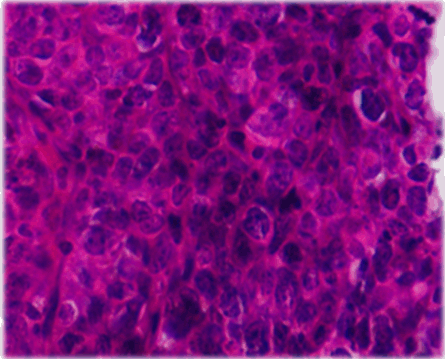

IA 40-year-old male with history of hypothyroidism, taking tab levothyroxine 100 mg once daily since one year presented to our hospital with the presenting complaint of a swelling in left side of neck, with progressive increase in size since last two months. On examination, a diffuse non tender lump measuring 6×3 cm in root of left side neck, moving with deglutition was noted with no palpable lymphadenopathy elsewhere. Serum T3, T4 and TSH levels were within normal limits. All other routine blood investigations were normal. Ultrasonography (USG) of neck showed mixed echogenic mass lesion in left lobe thyroid measuring 56x29 mm. Ultrasonography guided fine-needle aspiration cytology from the left lobe of thyroid lesion showed lymphoid large mononuclear cells. Trucut biopsy from the left thyroid lobe lesion was suggestive of non-Hodgkin’s lymphoma as lymphoid tissue with diffuse medium to large sized atypical cells with prominent round nucleoli and condensed chromatin with scanty cytoplasm and mitotic figures were present (Figure 1). Immunohistochemical analysis was reported as CD20 strongly positive, MIB-1 labeling index 60–65%, CD3 negative, CD5 negative, CD10 negative, CD23 negative, cycline D1 negative and Pan-Cytokeratin negative, suggestive of diffuse large B cell lymphoma (DLBCL) thyroid (Figure 2). The PET-CT scan showed FDG avid hypodense mass lesion involving the left lobe of thyroid gland measuring 63x38x31 mm with SUV Max 31.11 with no evidence of other abnormal lesion in the body (Figure 3). Bone marrow aspirate and biopsy were normal. Based on these investigations, final diagnosis was non-Hodgkin’s lymphoma-Thyroid (DLBCL, stage IEA).

Figure 1: Lymphoid tissue with diffuse medium to large sized atypical cells with prominent round nucleoli and condensed chromatin with scanty cytoplasm and mitotic figures (H&E stain, x400).